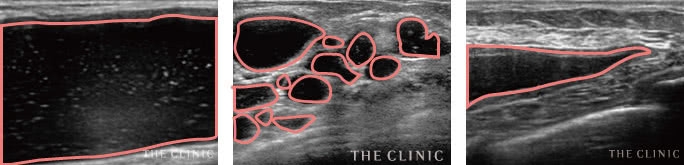

(1)エコー検査でバストの中のヒアルロン酸の状態をチェックします。

(2)ヒアルロン酸の位置を確認しながら、残らず丁寧に除去します。

(3)術後に再度エコー検査を行い、確実にヒアルロン酸がなくなっていることを確認いただきます。

特に多いのが「しこり」のお悩みです。ヒアルロン酸は、通常一定期間で体内に吸収されていきます。ただ、体質などによっては硬いしこりとして体内に残ってしまうことがあるのです。このような場合、当院では乳腺専用のエコーでしこりの位置を確認した上で、一つ一つ手作業で取り出していきます。

今回ご紹介する「ヒアルロン酸除去外来」でもエコー検査を併用し、ヒアルロン酸を残らず丁寧に除去していきます。健康と安全を第一に考え、みなさまの不安を解消するためのお手伝いができれば幸いです。